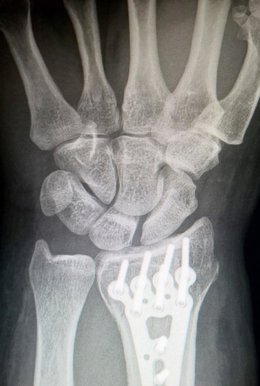

Distracción ósea.

Concretamente, el estudio se ha centrado en la osteogénesis por distracción ósea, un procedimiento de reconstrucción en el que se utiliza un elemento externo denominado distractor que separa gradualmente el hueso. Este mecanismo transmite fuerzas de tracción sobre el callo que se va formando para conectar la fractura y así consigue un estiramiento que produce la formación de nuevo tejido entre las superficies de los segmentos separados.